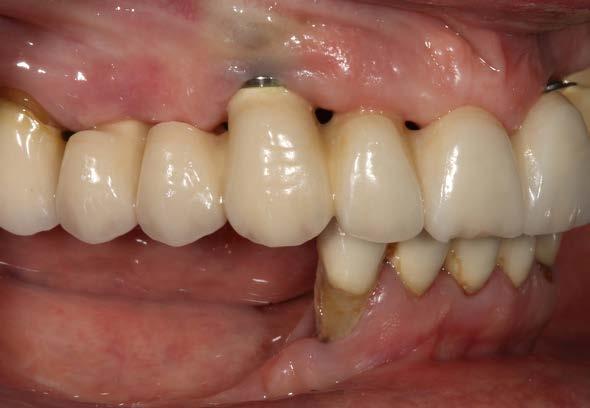

Figuras 2 y 3. Imágenes intraorales de la paciente, donde podemos observar la pérdida ósea acusada en algunos puntos con exposición de los componentes protésicos, así como transparencia incluso de las espiras de los implantes como el situado en posición 13 a través del tejido gingival.